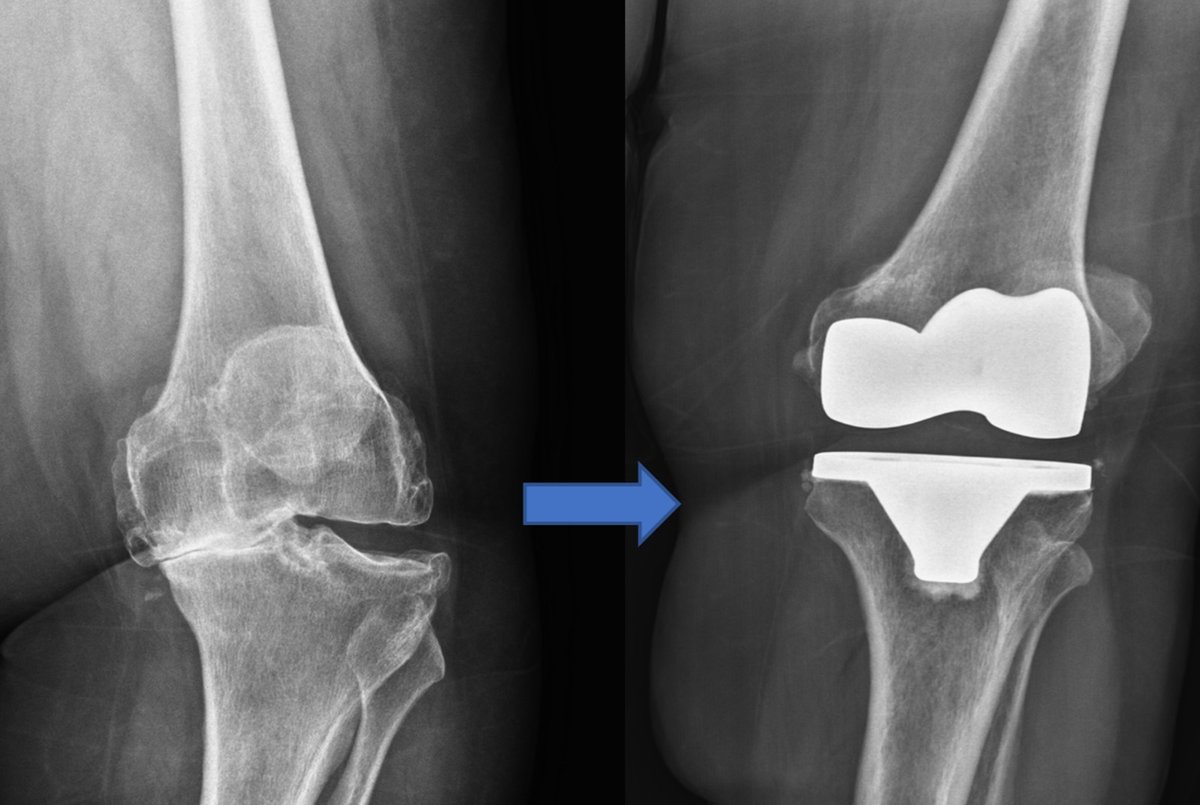

حول كاريا جراحة العظام وإعادة التأهيل عيادة كاريا جراحة العظام وإعادة التأهيل في موغلا ، تركيا تقدم رعاية العظام عالية الجودة ، بما في ذلك العلاجات الجراحية وغير الجراحية من قبل Assoc. البروفيسور الدكتور جيم يالين KILIN وفريقه. وهم متخصصون في الصدمات والإصابات الرياضية وجراحات تقويم المفاصل ، ولديهم خبرة في العلاج الطبيعي لإعادة التأهيل.